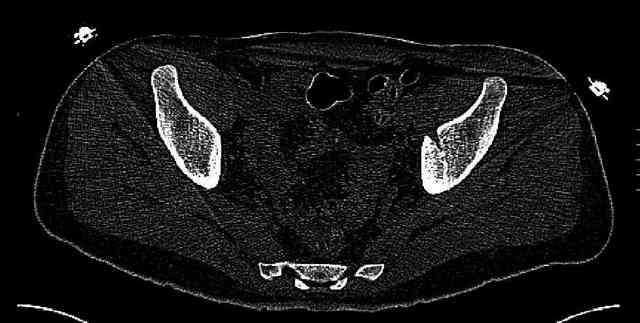

The last two images from the 3-D CT scan certainly makes the fracture look worse than the plan radiographs.

Some more images. Does it help to guess which part of the acetabulum is displaced?

Normal appearing SI joints and a healed posterior column limb... my bet's on caudal segment displacement.